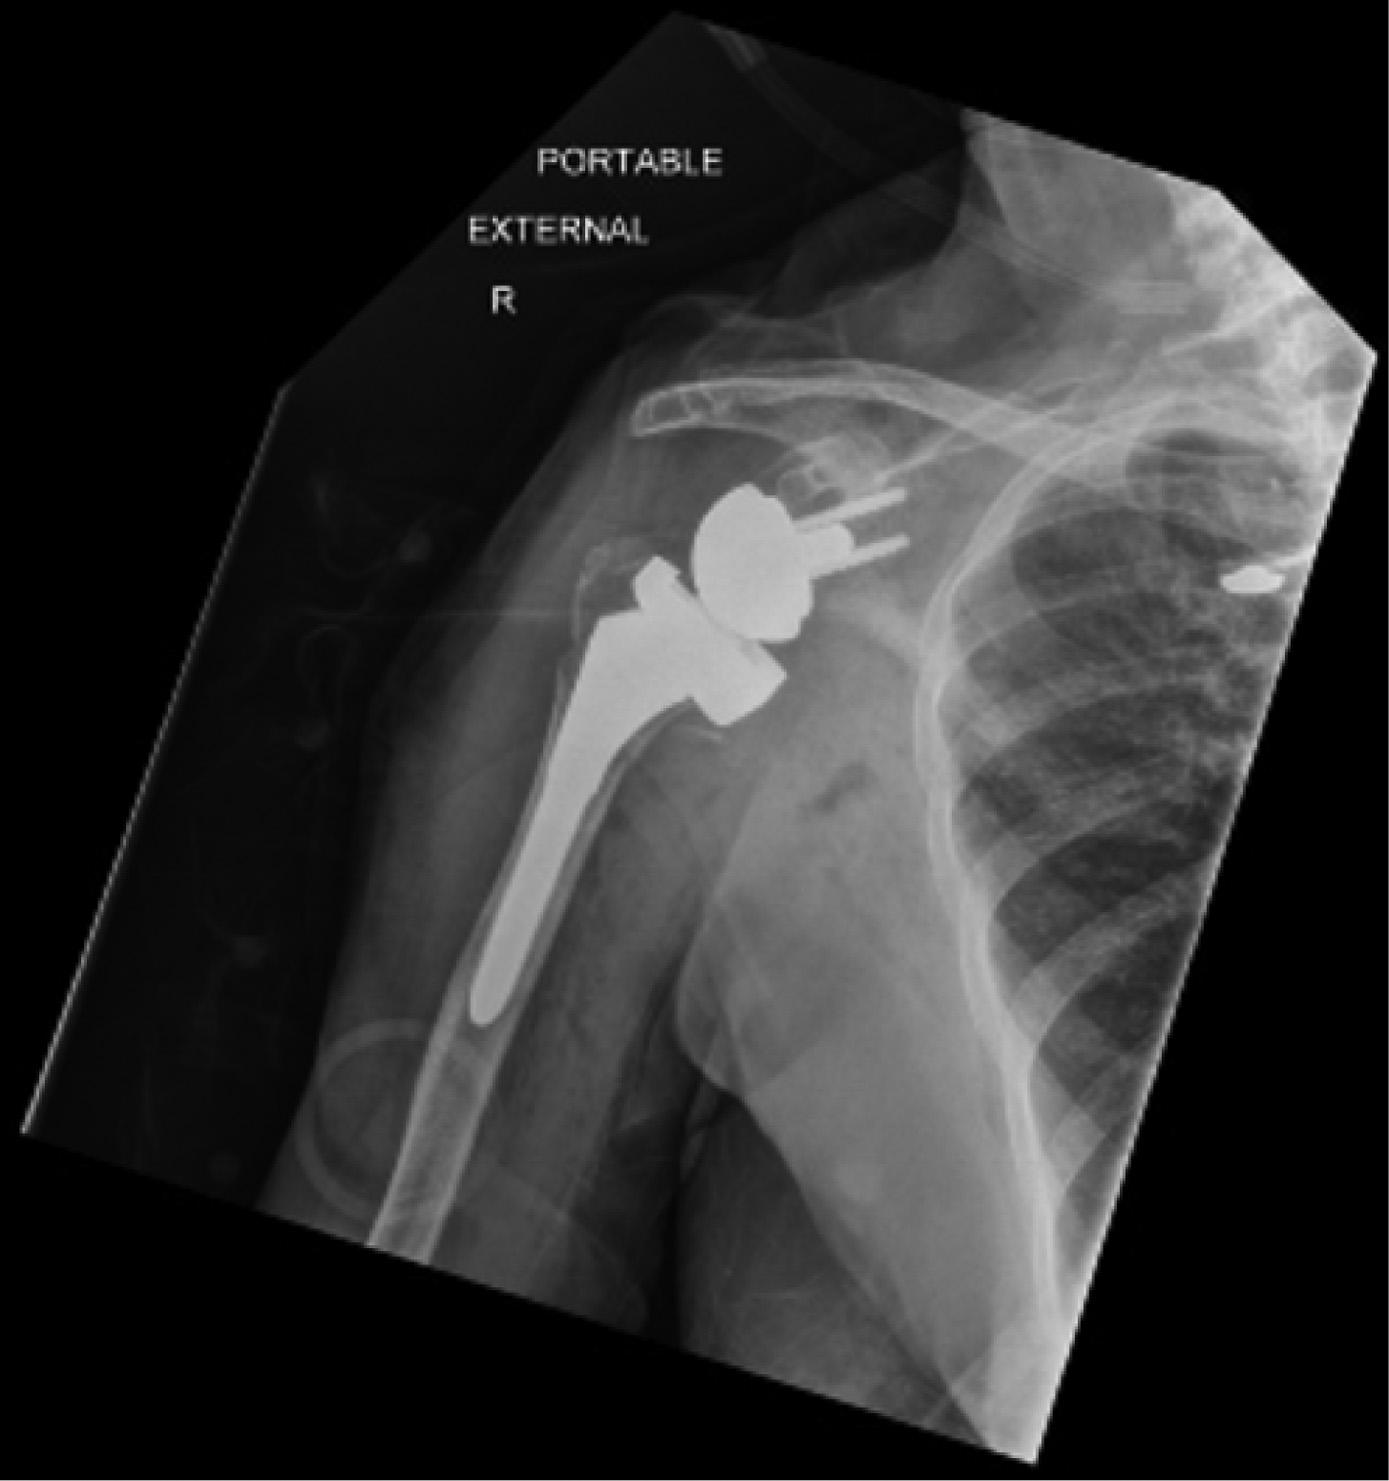

ThepatientunderwentanemergentCTofthehead (Image3)duetothechangeinmentalstatus.Theradiology impressionoftheCTrevealed “extensivevenousgas,which

Computedtomographyofthebrainofa77-year-oldman afterarapidchangeinmentalstatusshowingextensivevenous gas(whitearrows)intherightparieto-occipitalregion.

mayindicategasemboluswithpossibleevolvinginfarctionin therightparietalregion.Nohemorrhageorshift.Further evaluationwithmagneticresonanceimaging[MRI]maybe useful.Largegoiter.” Immediatelytheteamassessedthe patient’scentralvenouscatheterandfoundanuncappedline. Aftertheairwaswithdrawnfromtheline,thelinewas capped.Thepatientwastransferredtotheintensivecareunit atourhospitalforfurthermanagementandahyperbaric medicineconsultation.Heunderwentahyperbaricoxygen therapytreatmentwithresolutionofthegasontherepeatCT head.Afollow-upMRIrevealedmultifocalinfarctsin multiplevascularterritories.